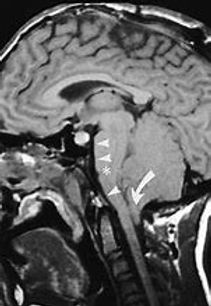

Chiari tipo I se caracteriza por el descenso de las amígdalas por debajo del foramen magno

Chiari tipo II presenta un descenso muy importante de las amígdalas cerebelosas, desaparición del 4 ventrículo y la cisterna magna, y en la mayoría de los casos de hidrocefalia. El Chiari II se presenta como parte de la evolución de un paciente portador de mielomeningocele.

Tratamiento quirúrgico

La cirugía consiste en realizar una ampliación del foramen magno por medio de una craniectomía occipital y ampliación de la duramadre subyacente con un injerto de aponeurosis o periostio de manera a reconstituir la cisterna magna. La cirugía se denomina craniectomía suboccipital